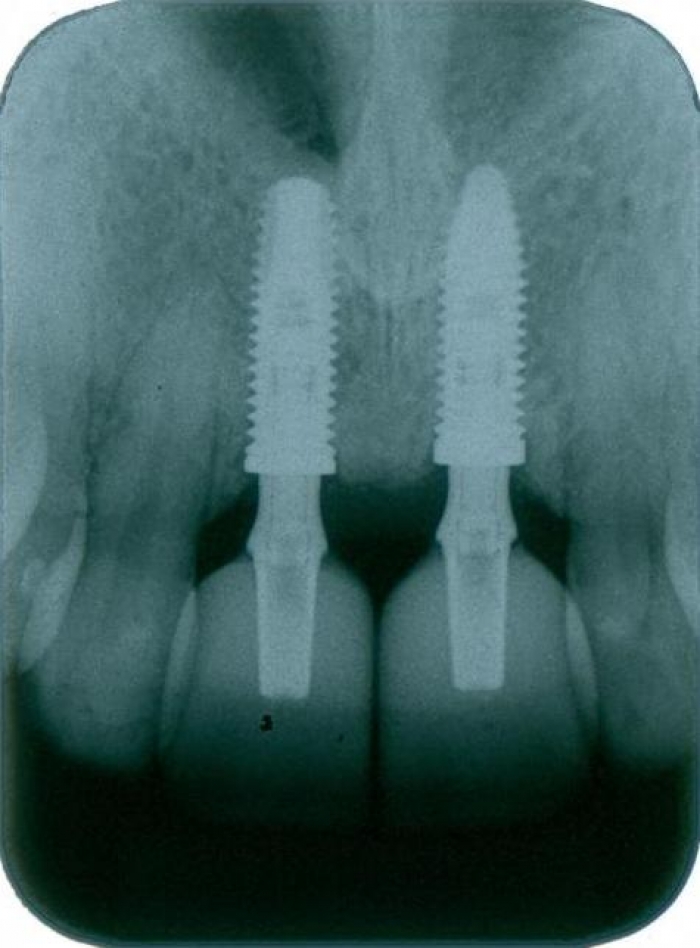

Raio - x Inicial 2013

Raio x em 2014, após enxerto em bloco com osso da mandíbula.